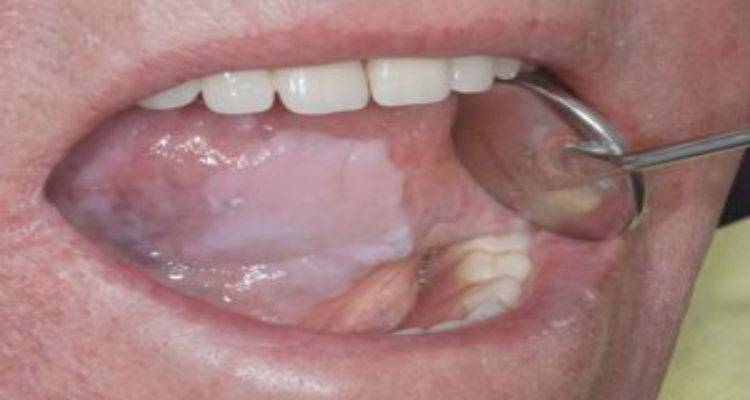

Είναι μια προκαρκινική βλάβη που εμφανίζεται στο βλεννογόνο του στόματος με τη μορφή λευκής πλάκας. Η πλάκα αυτή είναι προσκολλημένη πάνω στον βλεννογόνο του στόματος. Μελέτες που έχουν γίνει έχουν δείξει ότι το 85-90% των πασχόντων είναι μανιώδεις καπνιστές (ένα έως τρία πακέτα την ημέρα) τουλάχιστον μια δεκαετία και με ελλιπή στοματική υγιεινή.

Η λευκοπλακία είναι προκαρκινική κατάσταση, γεγονός που σημαίνει ότι αν δεν αντιμετωπιστεί εγκαίρως υπάρχει κίνδυνος να εξελιχθεί σε καρκίνο. Οι πιθανότητες διαφέρουν ανάλογα με το σημείο του στόματος όπου αναπτύσσεται η βλάβη. Έτσι έχουμε περιοχές «υψηλού κινδύνου», όπως το έδαφος του στόματος και η γλώσσα με πιθανότητες κακοήθους εξαλλαγής 15-20% και «χαμηλού κινδύνου», όπως τα ούλα με πιθανότητες 5-6%.